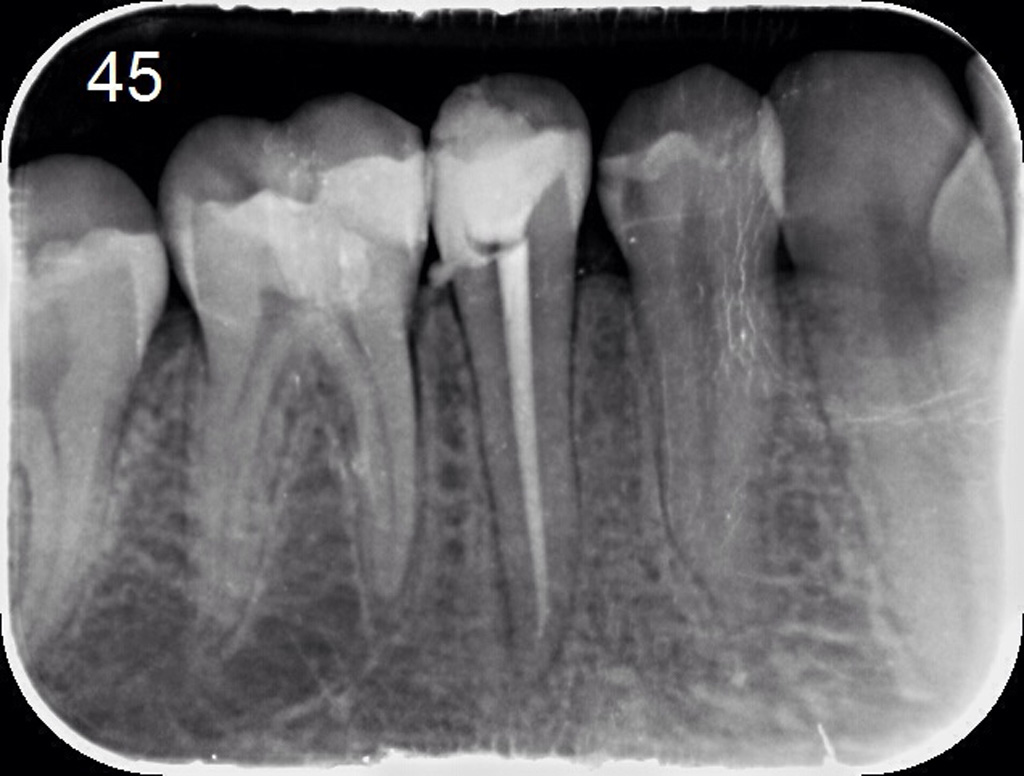

Lečenje zuba podrazumeva postupak uklanjanja nerva iz samog zuba. Naš tim se edukavao iz oblasti savremenih principa endodontske terapije i mašinske endodoncije kako bi svojim pacijetima ponudili najkvalitetnije usluge iz navedene oblasti.

Znanje i aparatura koju posedujemo omugućuje nam da obradu kanala korena zuba sprovodimo uoptrebom mašinskih rotirajućih instrumenata (ProtaperNext), irigansa propisanih od strane evropske asocijacije endodonata i savremnih tehnika punjenja kanala korena. Na taj način zubi su besprekorno izlečeni i traju dug vremenski period.